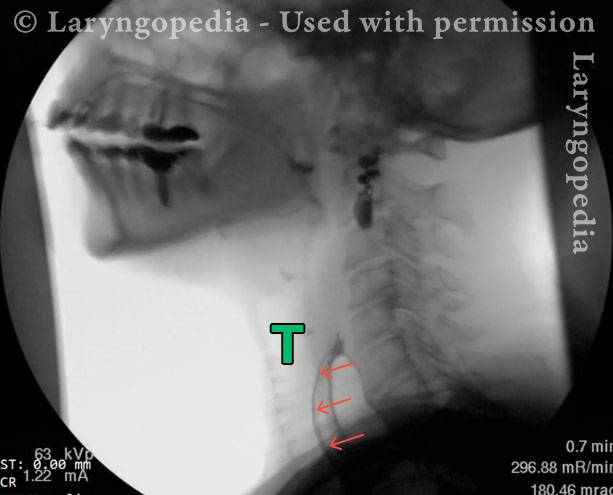

This visual series depicts a hallmark feature of R-CPD: marked dilation of the upper esophagus filled with swallowed and retained air. Normally, this air would be burped out, but in persons with R-CPD, it cannot be expelled.

The retained air can push upward, creating a sense of pressure and a distinct gagging or “throat nausea” sensation. It also explains a striking procedural observation: during office upper esophagoscopy, air insufflation is unnecessary, because the patient’s esophagus is already dilated by trapped air, allowing visualization of its walls.

Esophagus bulges anteriorly (3 of 4)